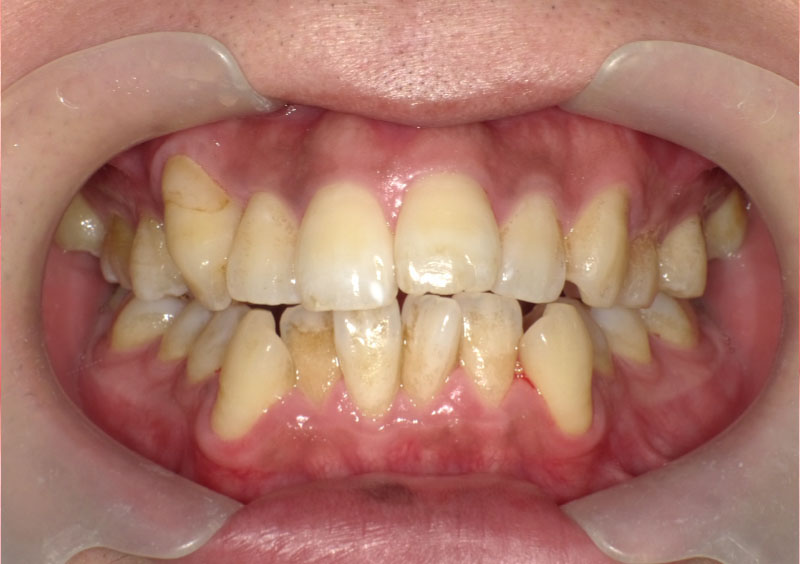

症例08

治療前

治療中

治療後

主訴 | 上の前歯をきれいにしたい。 |

治療期間 | 2年間 |

治療費 | ¥616,000(税込) |

治療内容 | 上下顎のインビザライン治療を実施。 4回の追加アライナーを用いて理想に 近づけた。 (追加アライナーの費用はありません) |

治療のリスク | 矯正に際して、智歯(親知らず)抜歯の 必要があり、抜歯に伴うリスクもあったが 経過に問題はなかった。 前歯のねじれが強くマウスピース単独での 治療にはリスクがあったが、細かく装置を 追加することで回避できた。 |